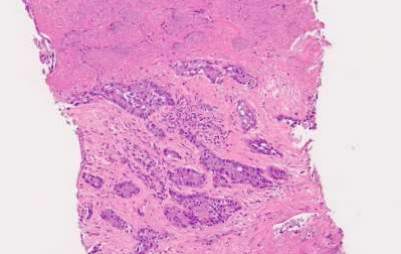

Fig.7: Left perinephric fat lesion.

Fig.8: Core biopsy from the left perinephric fat lesion.

Fig: Pan-CK highlighting the tumor cells in the left perinephric fat lesion.

The biopsy from the left perinephric lesion revealed deposits of an adenocarcinoma with remarkably similar morphology (nested and sheet-like pattern) (pink) and immunophenotypical characteristics to the prior bone biopsy viz. it too expressed epithelial markers (CK7, CK19)and HepPar1 (while still being negative for Glypican 3, TTF1, Napsin A, p63, p40, RCC, CD10, PSA, Calretinin, Melan A, Synaptophysin, chromogranin and CK20).

- Based on the perinephric lesion and bone biopsies, in view of the positivity for CK7 and CK19, a primary from the upper aero digestive tract or pancreaticobiliary tract was suggested. HepPar1 may be expressed in non-hepatic carcinomas and should be interpreted with caution. The extensive IHC panel ruled out primaries from liver, lung, kidney, prostate, lower gastrointestinal tract, melanoma, PEComa, neuroendocrine tumors and squamous cell carcinoma (SCC).

So, the patient had a SQUAMOUS lung lesion and an ADENOCARCINOMA from the left perinephric region. Suspecting a second malignancy, namely a gastrointestinal malignancy, on July 3,2023 a second colonoscopy was performed. It revealed a 4 mm sessile polyp in the mid transverse colon, 10 mm pedunculated polyps in the sigmoid colon, and 2 – 4 mm sessile polyps in the rectum. All were histopathologically benign.